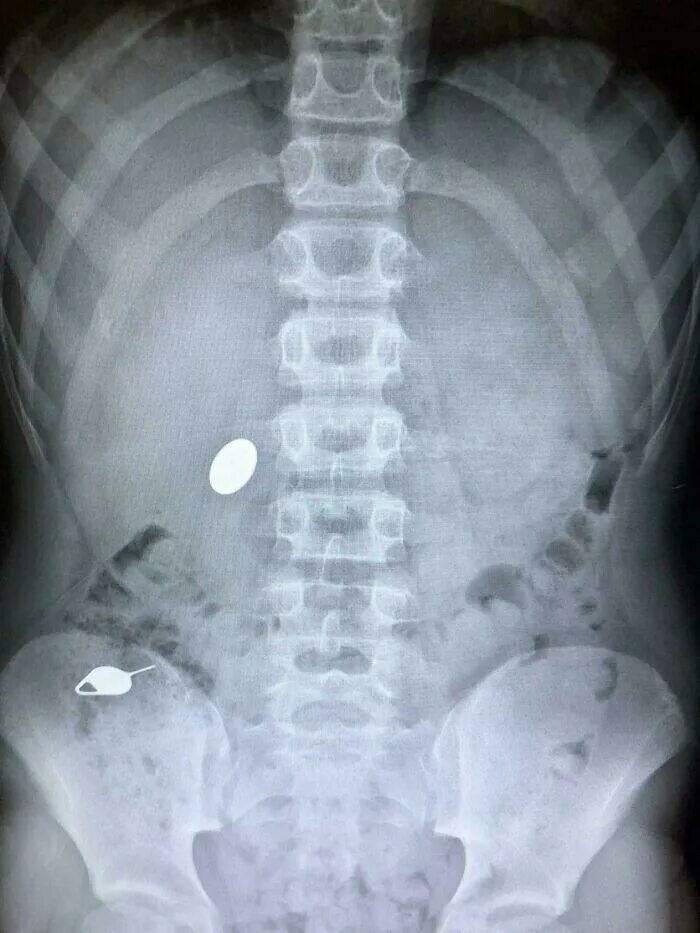

Что делать ребенку год проглотил монету